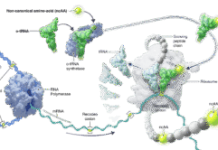

Several recent studies have found mechanisms that regulate the competing endogenous RNA (ceRNA) network affect the incidence and development of HCC. The ceRNA network is a complex post-transcriptional regulatory network where circular RNAs (circRNAs), long noncoding RNAs (lncRNAs) and protein-coding mRNAs compete with microRNAs (miRNAs) through at least one shared miRNA response element (MRE).

The researchers compare RNA sequencing data available in public TCGA and GEO databases to identify mRNAs, lncRNAs and circRNAs that are expressed at different levels in HCC and normal tissues and predict target miRNAs of differentially expressed (DE) circRNAs and lncRNAs to construct a prognostic circRNA-lncRNA-miRNA-mRNA ceRNA network for HCC. They establish a seven-gene HCC signature and validate one hub gene in the prognostic signature, DTYMK, as a new potential biomarker.

Based on the targeting relationships between 7 hub mRNAs and other RNAs, the researchers establish the prognostic ceRNA network of 21 circRNAs, 15 lncRNAs, 5 miRNAs, and 7 mRNAs.